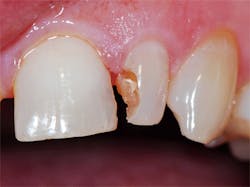

G-Premio Bond (GC America Inc.), a new universal eighth-generation bonding agent, was applied with a microbrush to all enamel and dentin surfaces and left undisturbed for 10 seconds. (figure 3). This was followed by application of a light air stream from the air/water syringe for 5 seconds to aid the evaporation of any remaining solvent in the adhesive, and then the bonding agent was light cured for 20 seconds. To ensure a thorough coating, a second coating of the adhesive was applied to the dentin areas of the prep and light cured.

A glossy surface on the dentin indicates that adhesive is fully coating the surface to be bonded. If any areas do not appear glossy, additional applications of G-Premio Bond can be applied. G-Premio Bond is compatible with total-etch, self-etch, and selective-etch techniques, providing excellent versatility for whichever technique the situation requires or the practitioner prefers.

Figure 3: G-Premio Bond was applied to the dentin and enamel margins and light cured for 20 seconds.